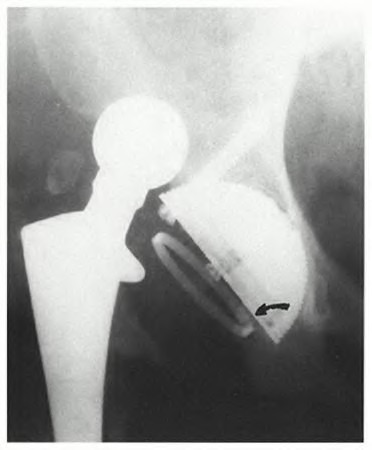

A 67-year-old man who underwent total hip arthroplasty (THA) 4 years ago fell on to his right hip. His pre-injury right hip film is seen in Figure A while films of his current injury are seen in Figures B and C. Prior to the fall he had no thigh or hip pain. His ESR and CRP are within normal limits. During intraoperative assessment, the acetabular and femoral stems are found to be well fixed. What is the next best course of action?

1) Revision of the acetabular component and ORIF of the femur with locking plates and cerclage wires

2) Revison of the femoral component, bypassing the fracture by two cortical diameters

3) Revision of the femoral component with impaction grafting and cerclage wires

4) Revision to a cemented component, bypassing the fracture by two cortical diameters

5) ORIF of the femur with locking plates and cerclage wires

This patient has a periprosthetic hip fracture at the level of the stem with a stable prosthesis, indicated open reduction and internal fixation as the treatment of choice.

The Vancouver Classification can be helpful in clinical decision-making regarding fixation versus revision of periprosthetic hip fractures of the proximal femur. A stable implant, by nature, does not need to be revised in the setting of adequate bone stock for fixation, but the ultimate test of stability should be in the operating room. Many fixation strategies are appropriate, but many implants include locking plate fixation for concerns of stress-shielded bone around the implant as well as use of unicortical fixation at the level of the stem.

Pike et al review the current trends in treating B1 fractures including locking plates with strut allografts, minimally invasive plate osteosynthesis (MIPO) and locking plates spanning femoral THA and TKA stems in selected patients. The authors conclude that no studies currently provide evidence establishing one

technique over the other and recommend treatment on a case by case basis.

Illustration A shows a possible fixation construct for this patient's fracture. The Vancouver Classification is seen in Illustration B and Illustration C represents an algorithm for treatment options.